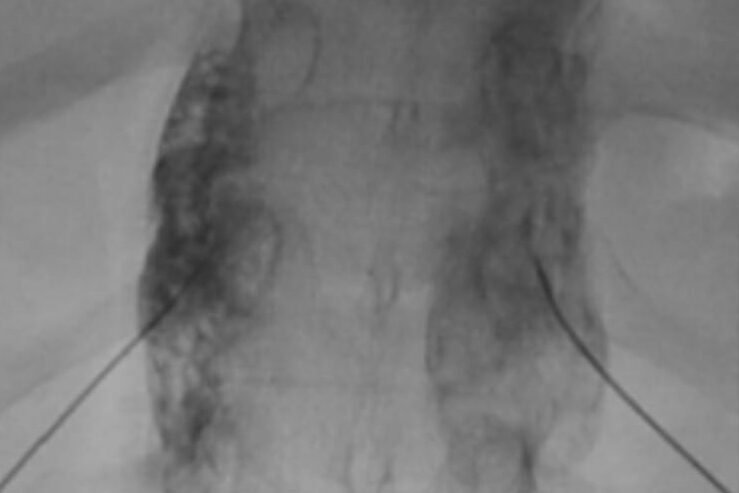

Imaging guided blocks:

- Intercostal nerve block

- Coeliac plexus neurolysis

- Superior hypogastric plexus neurolysis

- Thoracic sympathetic ganglion block

- Vertebroplasty

Imaging guided blocks